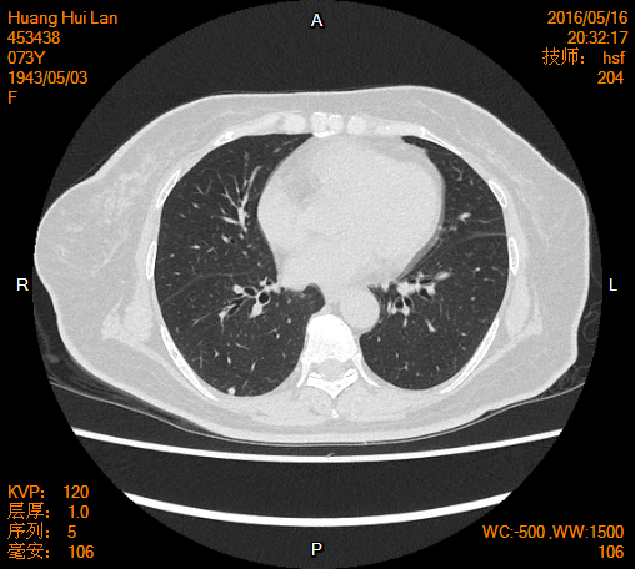

2016-04-13胸腹盆CT

2016-05-17胸腹盆CT(术后基线)